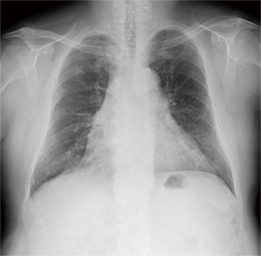

X線動態画像(図2)では,右上肺野の結節と5本の肋骨はずれて動き,肺野の血管もよく動くことから,癒着はないと判断した。手術所見では,上肺野の結節部分には予測どおり癒着はなかったが,横隔膜面に粗大な癒着が認められた。特に立位でX線動態撮影を行う場合には,横隔膜上に肺が乗って呼吸移動するため,横隔膜面の癒着をとらえることは困難であると考えられる。

図2 症例2:癒着の予測が困難な症例